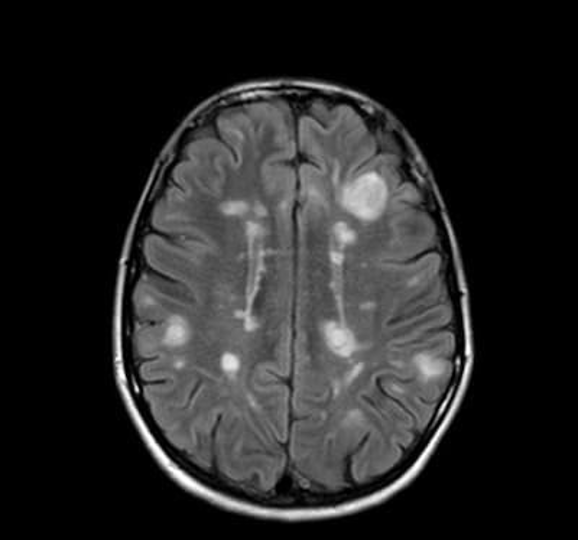

В исследовании, опубликованном в JAMA Neurology, представили результаты пятилетнего наблюдения за пациентами с рассеянным склерозом, получающими терапию в виде ублитуксимаба – моноклонального антителанового поколения, нацеленного на B-клетки. Оказалось, что непрерывное лечение ублитуксимабом в течение пяти лет приводит к практически полному подавлению обострений и значительно снижает риск большей инвалидизации. Credit: public domain Рассеянный склероз – заболевание центральной нервной системы (ЦНС), при котором собственная иммунная система пациента атакует зрелые олигодендроциты (глиальные клетки, которые образуют миелиновую оболочку аксонов клеток ЦНС) и разрушает их. Раньше считалось, что B-клетки и Т-клетки играют ключевую роль в патогенезе рассеянного склероза. Также мы писали о роли олигодендроглии (состоящей из различных типов олигодендроцитов), которая может переходить в состояние, связанное с заболеванием. Для лечения рассеянного склероза на первых этапах часто применяют препа